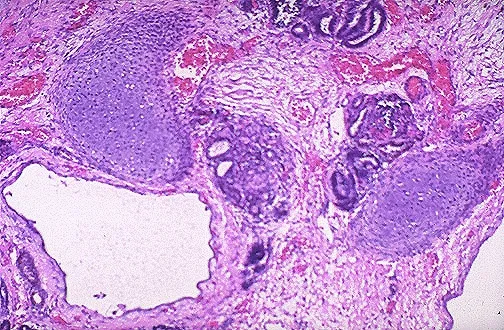

- Multicystic Dysplastic Kidney (MCDK): Sporadic, non-hereditary anomaly where the kidney is replaced by non-communicating cysts.

- Histology: Cysts are lined by flattened epithelium, surrounded by undifferentiated mesenchyme and islands of cartilage.

⭐ Exam Favorite: Unilateral MCDK is a common cause of an abdominal mass in newborns. Bilateral involvement leads to Potter sequence and is incompatible with life.